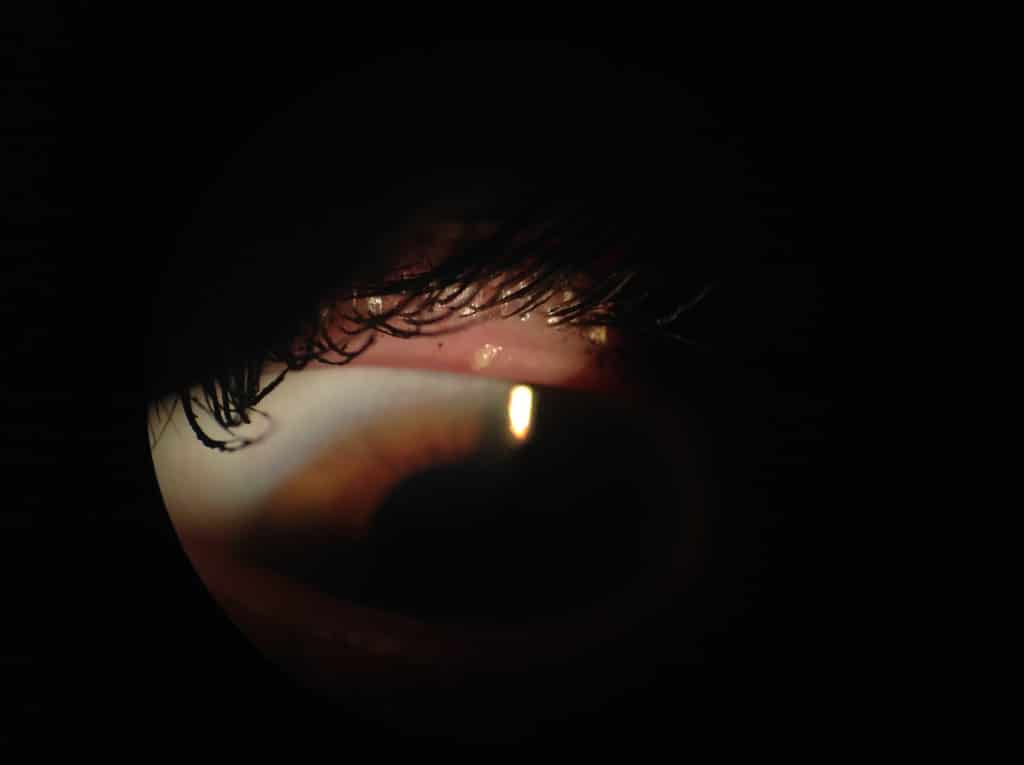

And here’s a good friend of mine who was tired of 2 week long goopy, red, irritated left eye. Yup-her glands are not happy especially that one right in the middle.